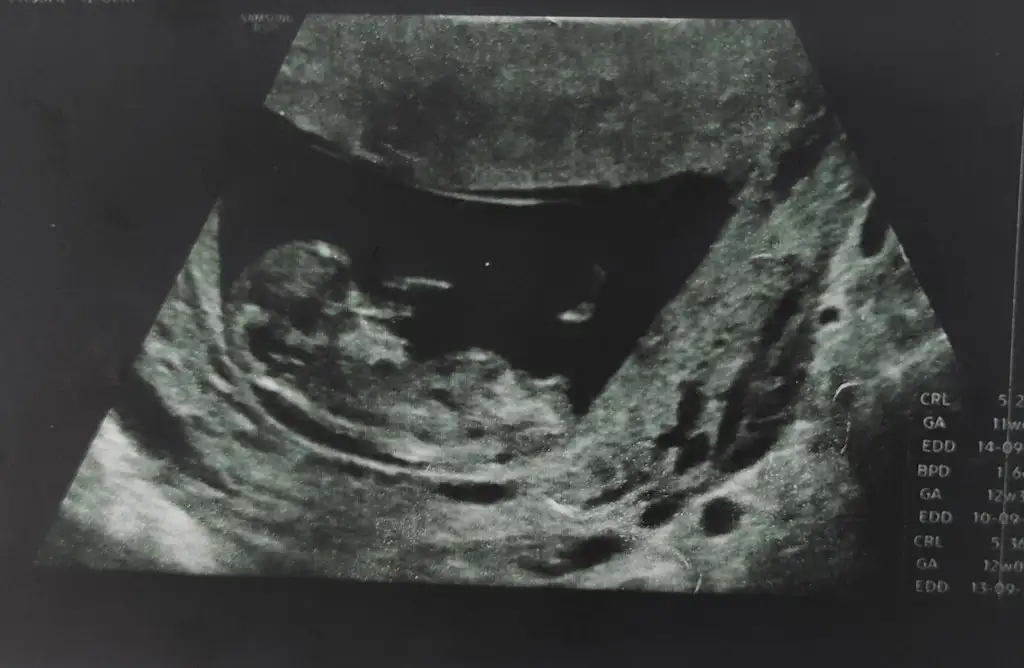

Merhaba, 12 haftalık karından ultroson ile bakıldı ☺️ cinsiyetini öğrenmek için 1 ayımız daha var. Sağlıklı olsun da önemli olan o ama insan merak etmiyor da değil. 9 yaşında da bi kızım var. Heycanla bekliyor kardeşini 😌